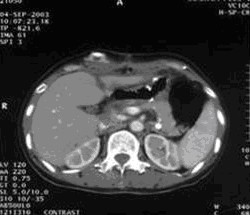

女,49岁。胃体癌晚期,胃窦增厚强化,与周围粘连,腹膜增厚,腹腔广泛转移,伴大量腹水。放/化疗失败,无法手术。治疗方案:腹腔灌注今又生2×1012VP/2次/周,共12周,同时灌注顺铂和5-氟尿嘧啶腹腔,后4周加8次全腹热疗。治疗后:第3周,腹水消失;第8周,胃窦、腹膜和网膜变薄,盆腔结节明显变小。后行手术切除残余胃肿瘤,术中探查全腹和盆腔未扪及肿瘤。术后病检胃肿瘤内未见癌细胞。

治疗中:第8周,腹水消失,胃壁变薄,盆腔结节明显变小